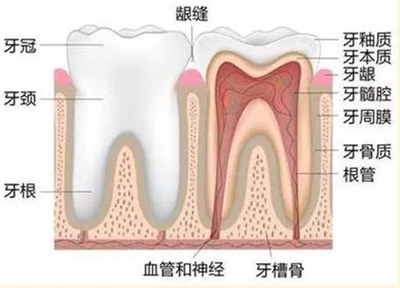

颜色非常接近人类牙齿的本来颜色。患者不能自行摘下,而是用水泥粘在磨好的牙齿上。瓷层颜色可根据患者邻牙颜色进行搭配,修复后美学效果一般较好。烤瓷牙口腔异味的危害由于烤瓷牙与真牙之间密封不彻底,食物残渣容易残留在牙齿内,牙齿内细菌代谢产生异味,容易形成口臭。受不了忽冷忽热* * *在医生配牙的过程中,牙医不小心磨坏了牙齿。

首先,如果选择一个靠谱的机构来做,危害是很小的。一般伤害都是为了便宜而选择不靠谱的烤瓷牙材料和技术不到位的医生造成的后续伤害。一、口腔不健康,易感染:不是每个人都适合做烤瓷牙。如果口腔环境不好(如牙周炎、牙龈出血、牙龈肿胀等。),很容易造成感染。另外,牙齿和牙冠密封不好,容易引起继发牙病。二、连体烤瓷牙容易引起继发牙病:一是连体烤瓷牙咀嚼时受力不均,更容易松动,给细菌可乘之机;二是制作烤瓷牙时,医生对牙齿的磨损过大,导致烤瓷牙冠离牙髓太近,容易诱发感染。

三、烤瓷牙材质引起过敏:非贵金属烤瓷牙是由镍铬合金制成,金属冠内外为高温瓷。由于其价格相对较低,目前在国内被广泛使用。但这种烤瓷牙有以下缺点:边缘紧密性差;与人体生物相容性差,部分患者佩戴一段时间后,颈部周围牙龈组织会出现“黑线”。另外,国外甚至有医学报道这种烤瓷牙会引起过敏反应,所以临床上很容易出现崩瓷。

烤瓷牙有哪些危害?烤瓷牙主要存在牙龈着色、真牙龋坏、咬合痛、颞下颌关节紊乱、崩瓷、冷热刺激痛等问题。烤瓷牙的危害现在越来越多的人会做烤瓷牙,但是如果不去正规的医院做烤瓷牙,会带来一些危害。那么烤瓷牙有哪些危害呢?以下是相关专家的详细解答。1.金属烤瓷修复体颈缘黑线(牙龈染色)问题使牙龈变黑,这是用非贵金属(镍铬合金、钴铬合金、纯钛)制作烤瓷牙的常见并发症,处理起来非常困难。

这样的烤瓷牙一定要拔掉重做,否则时间久了会引起牙龈炎,逐渐发展成牙周炎,导致牙齿松动脱落。2.真牙的龋齿磨制不合格,牙模不精致,加工厂技术不到位,会导致烤瓷牙和真牙连接不紧密(冠根间隙大)。使用一两年后就会变成细菌的仓库!这时候刷牙,用漱口水,牙线都没用。隐藏在烤瓷牙和真牙之间的细菌进入牙套,逐渐腐蚀真牙,导致真牙龋坏。时间久了,真牙甚至会彻底烂掉。